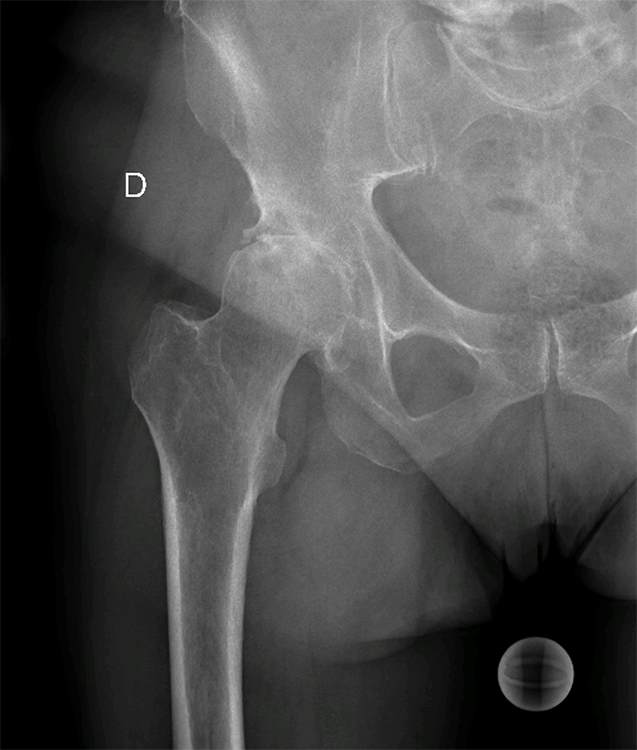

Pathologie : La Coxarthrose

Radiographie hanche de face avec coxarthrose avancée

- Dr Dumoulin